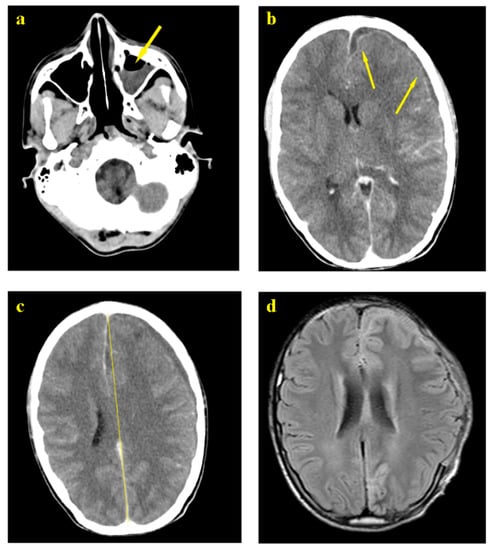

A non-injected brain CT scan on 22 January 2018 revealed the presence of sinusitis and a left holoencephalic millimeter hypodensity attributed, according to the treating specialist, to a thin blade of chronic subdural hematoma with his recommendations to treat it medically and conservatively (Figure 1a).

Despite the antibiotherapy with 1 g of Ceftriaxone IV twice a day through IV, the patient continued to deteriorate neurologically, with crises that became more frequent, a complete resolution of the state of consciousness imposing the need to intubate. A second scan revealed the stability of the subdural collection, but with a huge increase in the underlying edema that extended into the white matter but did not look like a glove. Moreover, a deviation of the median line of more than 1 cm was reported (Figure 1b).

A secondary diagnosis suggested the presence of empyema rather than hematoma. This hypothesis was ignored and conservative treatment was continued until bilateral mydriasis appeared along with abolition of reflex brainstem urging the necessity of a surgical procedure. A decompressive cranectomy with an enlargement duroplasty was performed and revealed a very abundant empyema consisting of encysted thick pus molding the cortical surface, infusing through the cortical sulcus and presenting multiple septa. With no significant complications, the surgery resulted in a complete resolution of mydriasis and restoration of the normal brain color and beating rhythm. No signs of meningitis were further identified in the brain MRI post decompression on 8 February 2018 (Figure 1c,d).

Figure 1. (a) Left ethmoid sinusitis; (b) Meningitis; (c) Meningitis and midline shift front to parietal collection; (d) Brain MRI post decompression (craniotomy).